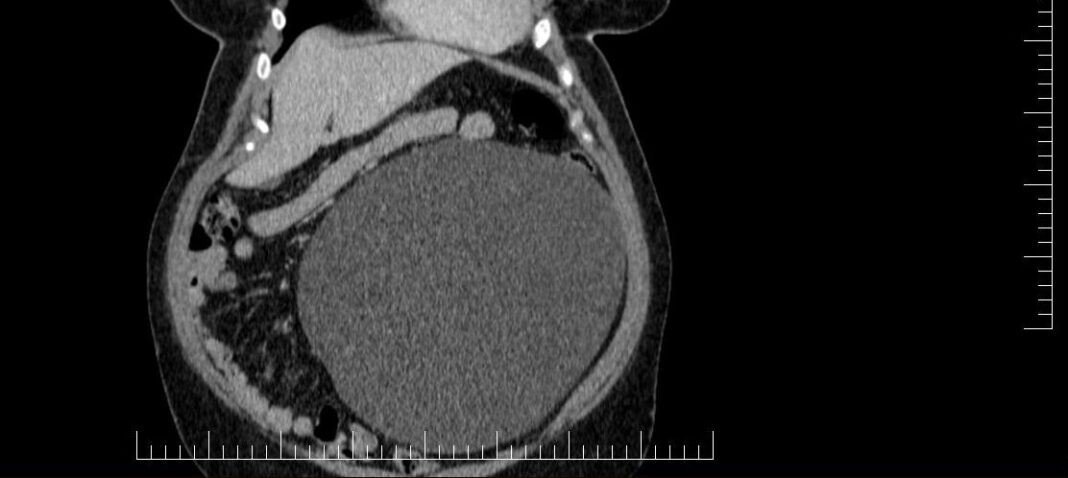

Un chist ovarian voluminos, de 4,5 kg, descoperit la o pacientă, în urma unui consult ginecologic și a unor investigații în cadrul Laboratorului radiologie și imagistică medicală al Spitalului Militar de Urgență ”Dr. Alexandru Augustin” din Sibiu, a fost operat cu succes de colegul nostru, Remus Maxim, medic primar obstetrică-ginecologie.

Existând suspiciunea de neoplasm, medicul din cadrul Compartimentului Ginecologie din Secția Chirurgie Generală a luat decizia de a extrage formațiunea chistică în întregime, operația fiind un succes.